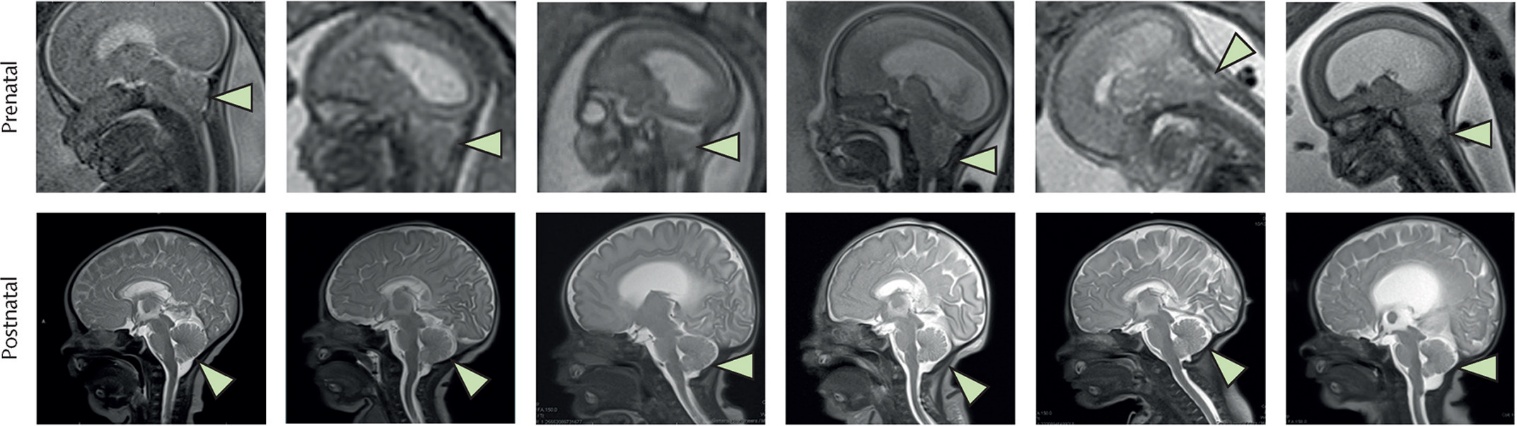

Khi sinh ra, tất cả các trẻ sơ sinh đều có vị trí vết mổ nguyên vẹn, không có dấu hiệu rò rỉ dịch não tủy, nhiễm trùng, vết thương hở hoặc tăng trưởng mô bất thường. Kết quả chụp cộng hưởng từ (MRI) sau khi sinh đã xác nhận rằng chứng thoát vị não sau – dị tật não liên quan đến tật nứt đốt sống, trong đó phần dưới của não trượt xuống vùng cổ – đã được khắc phục ở cả sáu trường hợp. Không trường hợp nào cần đặt ống dẫn lưu dịch não tủy để điều trị tràn dịch não, và tất cả đều được xuất viện mà không cần thở oxy tại nhà. Các nhà nghiên cứu không tìm thấy bất kỳ khối u hoặc sự tăng sinh mô bất thường nào. Các trẻ sơ sinh không gặp bất kỳ tác dụng phụ nghiêm trọng nào do điều trị tế bào gốc trong suốt quá trình điều trị và theo dõi (kéo dài đến 6 tuổi). Việc theo dõi thời gian dài giúp các nhà nghiên cứu khẳng định PMSC an toàn và cải thiện khả năng vận động, sức khỏe và chất lượng cuộc sống của trẻ khi lớn lên.

Kết quả chụp cộng hưởng từ (MRI) sau khi sinh cho thấy chứng thoát vị não sau đã được khắc phục ở cả sáu trường hợp